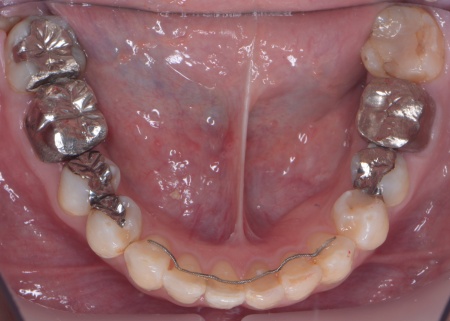

次にアンカースクリューを埋入し、上下の歯にワイヤー矯正装置を装着して、少しずつ歯を動かしました。

治療の結果、前歯が正しく噛み合うようになり、横顔のバランスも整いました。

矯正治療終了後は、歯が元の場所に戻らないよう上下前歯に保定装置(リテーナー)を装着し、治療を終了しています。